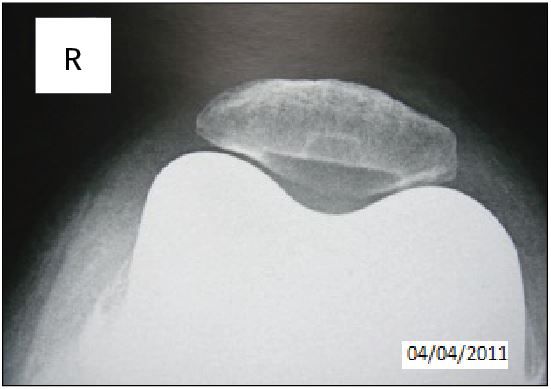

Patellofemoral tracking

2 of the 145 patients (1.3%) presented with a patellar shift of more than 3 mm. Both patients presented preoperatively with lateral subluxation of the patella. 3 patients (2 %) presented with a patellar tilt of more than 10°. All other knees –demonstrated a perfectly centred patella (Figure 10).

The outcomes of patellofemoral tracking assessed on Merchant’s views at 30 and 60° appeared to be most satisfactory, compared with those usually published in the literature (12). If this study does not aim to prove that trochlear navigation improves the clinical outcome of a total knee arthroplasty, it does seem to demonstrate that the technique allows the percentage of patellofemoral complications (shifting, tilting or subluxation) to be decreased